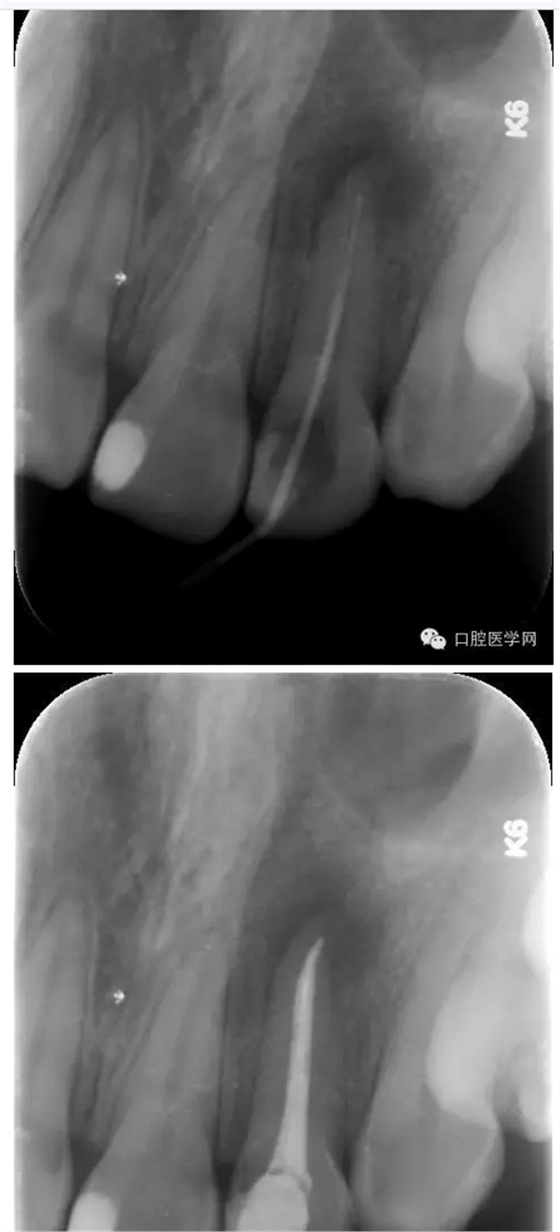

治療:第一次:去舊充填體,去腐質(zhì),GG鉆去除牙膠充填體,疏通根管,測(cè)量工作長(zhǎng)短,H銼與K銼去除剩余牙膠,雙氧水和鹽水大量沖洗,機(jī)擴(kuò)至S1,超聲蕩洗,激光行根管消毒,封CP球。

第二次:復(fù)診無(wú)不適,回去后疼痛即刻解除。叩診無(wú)不適。無(wú)松動(dòng)。處置:去暫封,見根管內(nèi)無(wú)滲出,機(jī)擴(kuò)至F2,雙氧水和鹽水大量沖洗,超聲蕩洗,激光蕩洗加消毒,干燥,封氫氧化鈣。

第三次:復(fù)診無(wú)不適。叩診無(wú)不適,無(wú)松動(dòng)。處置:去除暫封物,鹽水沖洗,試尖,牙膠尖+AHplus糊劑冷測(cè)壓充填,玻璃離子體充填。